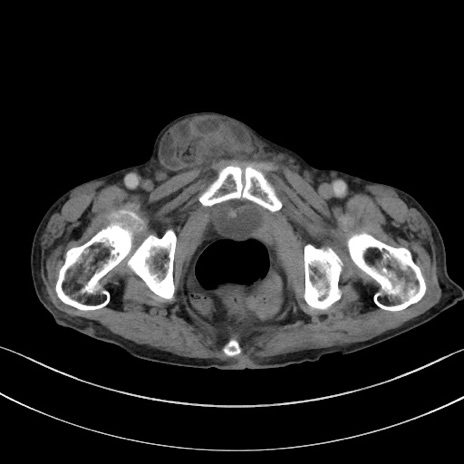

症例3(横断像)

症例

【症例】 70歳代男性

【主訴】右鼠径部腫瘤、疼痛

【現病歴】本日朝より上記主訴あり、受診。

【既往歴】膀胱癌にて膀胱全摘、両側尿管皮膚瘻

【データ】WBC 5600、CRP 0.56